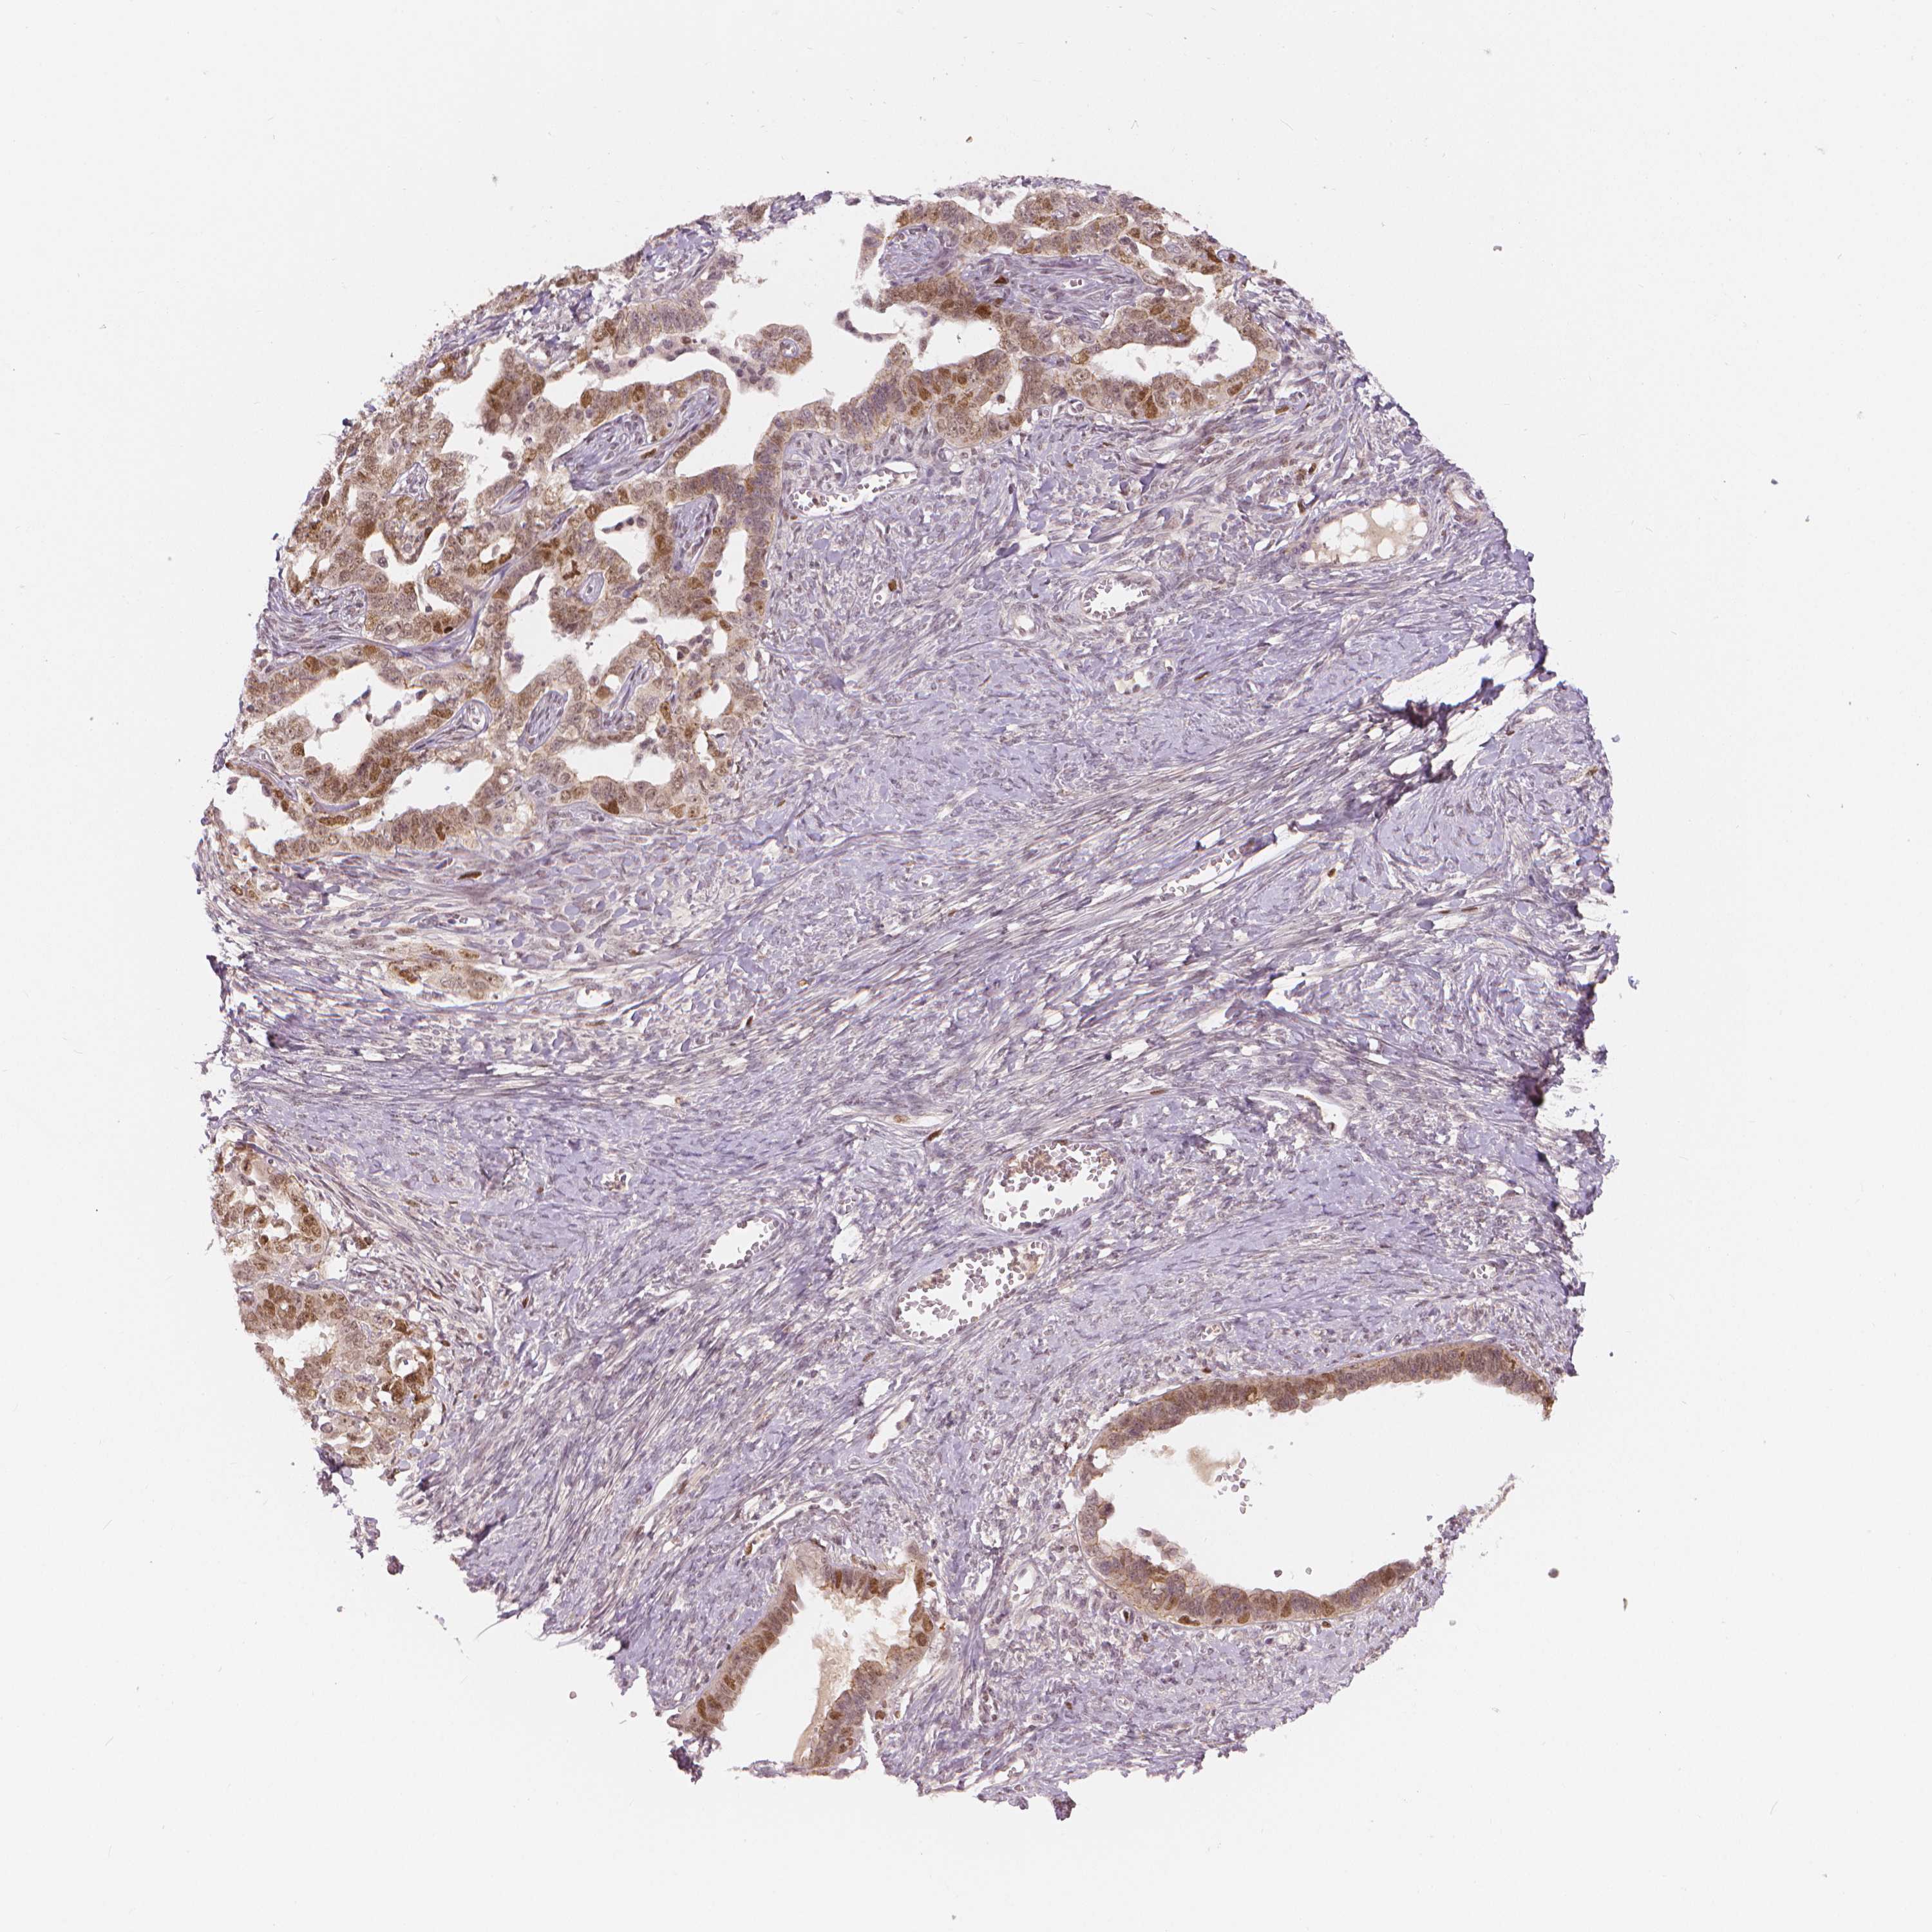

OVARIAN CANCER - Protein expressioni

A mouse-over function shows sample information and annotation data. Click on an image to view it in a full screen mode. Samples can be filtered based on level of antibody staining by selecting one or several of the following categories: high, medium, low and not detected. The assay and annotation is described here.

Note that samples used for immunohistochemistry by the Human Protein Atlas do not correspond to samples in the TCGA dataset.

Antibody stainingi

Antibody staining in the annotated cell types in the current human tissue is reported as not detected, low, medium, or high, based on conventional immunohistochemistry profiling in selected tissues. This score is based on the combination of the staining intensity and fraction of stained cells.

Each image is clickable and will lead to virtual microscopy that enables deeper exploration of all samples and also displays staining intensity scores, fraction scores and subcellular localization as well as patient and tissue information for each sample.

Antibody HPA015801

Antibody CAB068246

Antibody CAB068247

Staining

High

Medium

Low

Not detected

Intensity

Strong

Moderate

Weak

Negative

Quantity

>75%

75%-25%

<25%

None

Location

Nuclear

Cytoplasmic/membranous

Cytoplasmic/membranous,nuclear

Cystadenocarcinoma, serous, NOS

Cystadenocarcinoma, mucinous, NOS

Carcinoma, endometroid